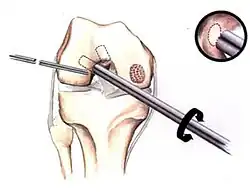

Similar to OATS, arthroscopic articular cartilage paste grafting is a surgical procedure offering cost-effective, long-lasting results for stage IV lesions. A bone and cartilage paste derived from crushed plugs of the non-weight-bearing intercondylar notch can achieve pain relief, repair damaged tissue, and restore function.[61]

Morselization of the articular cartilage lesion

Harvesting of the articular cartilage and bone

Manual crushing used to make a paste graft

Impacting the paste graft into the morselized defect